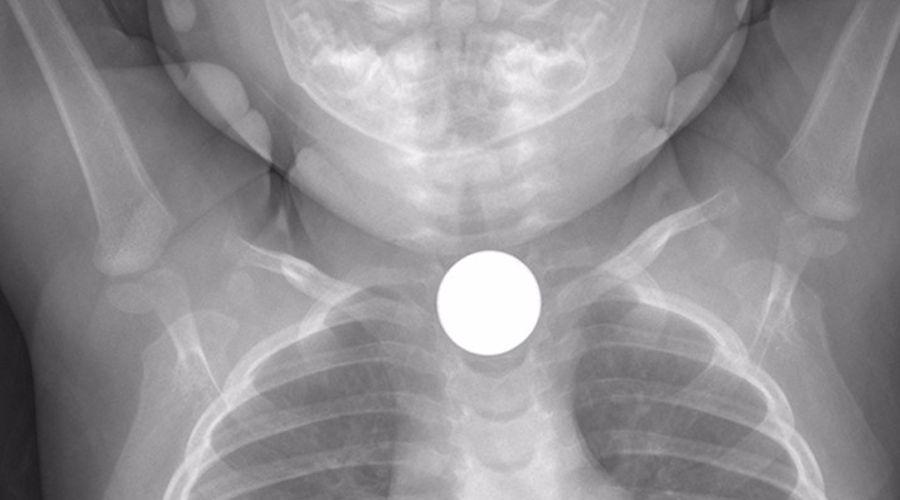

Según fuentes consultadas, el hecho se produjo cerca de las 22 en la vivienda de la nena, cuando se encontraba jugando con una moneda de un peso.

Trascendió que en un descuido de los padres la niña tragó la moneda, ellos notaron que su hija no podía respirar, acción que preocupó a los padres quienes la llevaron de inmediato al hospital Zonal de Termas.

La misma fuente indicó que debido a la complejidad del caso, la menor fue trasladada al Cepsi donde se encuentra internada.